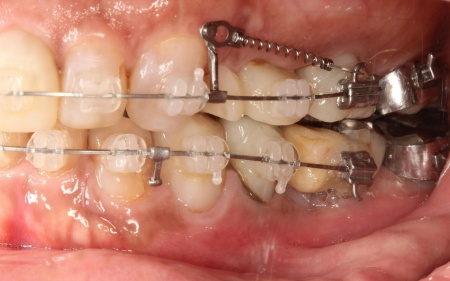

まずは、口腔内全体の矯正治療から開始します。

上顎は左上の歯が欠損していたため、左右のバランスを整える目的で、右上の歯(第1小臼歯)を抜きました。

その後、ワイヤー矯正とクローズドコイル(バネの装置)を使ったスピード矯正を行い、前歯を後方に移動させます。

下顎は残根も利用しながら、矯正用の小さなネジ「テンポラリーインプラント(インプラントアンカー)」を顎の骨に埋め込んで固定源とする方法も併用し、歯を移動させました。

矯正期間中は定期的に装置の調整を行い、歯の動きや噛み合わせの変化を確認しながら治療を進めています。